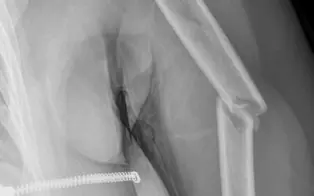

Fracture de la diaphyse humerale